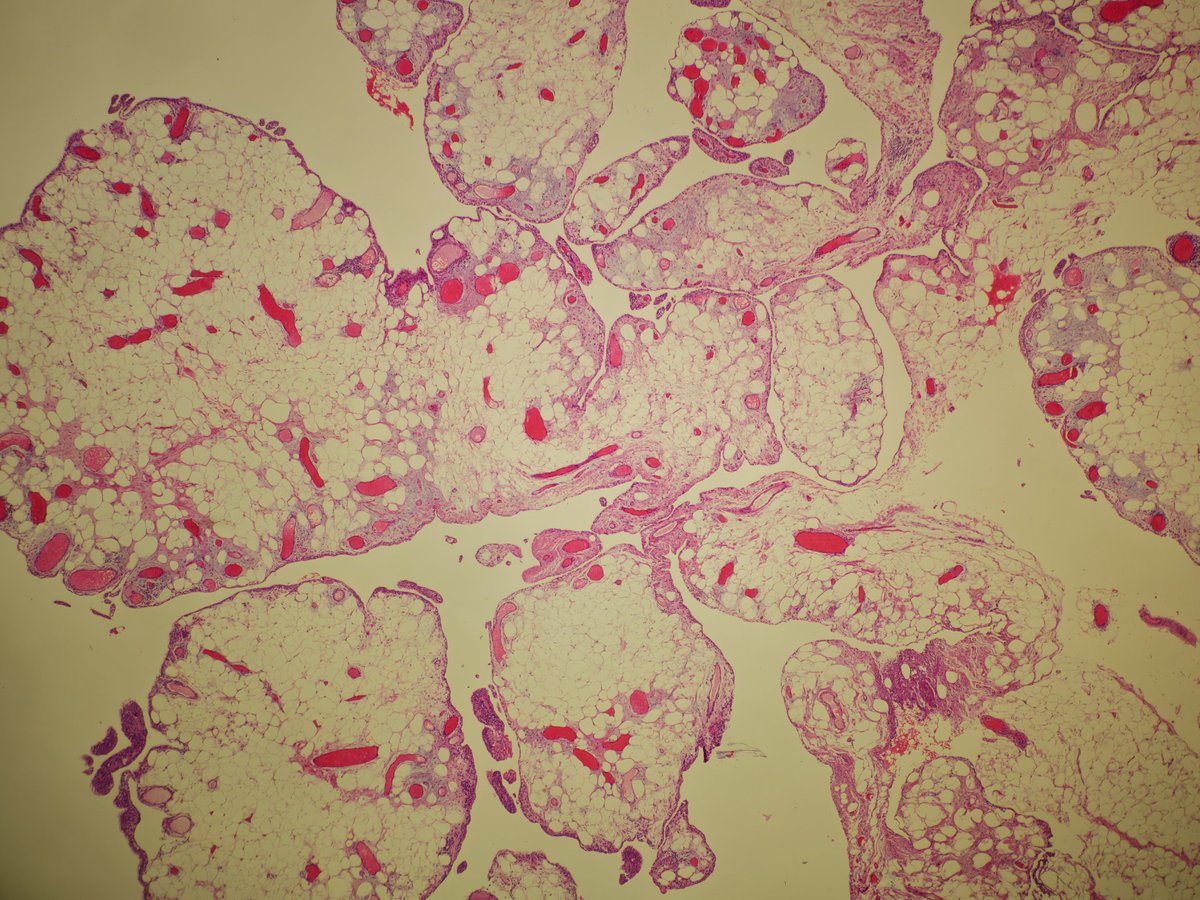

Synovial lipomatosis (lipoma arborescens, Hoffa's disease)

➡️Mature unremarkable fat extending to the partly hyperplastic synovial lining, imparting a villiform/papillary architecture

➡️Scattered chronic inflammation

➡️M>F, usually knee joint

#BSTPath #PathTwitter #pathoutpic